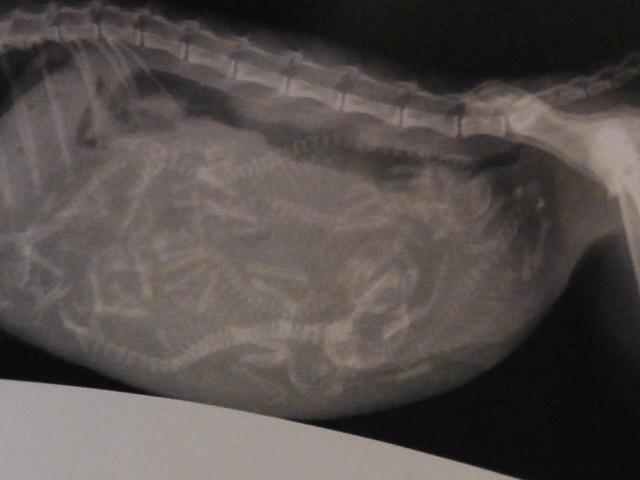

отвечая на вопросы серьезного содержания, решила добавить логику, медицину, науку.

вот бы всем на н.г такой прибор!

теперь вскрывать и ломать не нужно

что к чему относиться

и даже такое интересующее ее обстоятельство раз и навсегда расставило все точки с помощью рентгена

новое понятие-желудочный сок